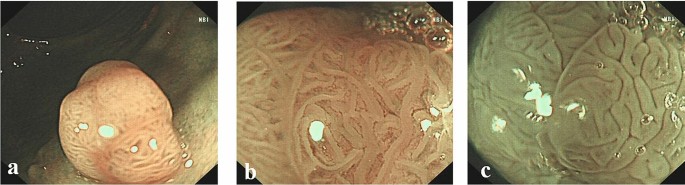

Surface patterns of neoplastic polyps viewed by different modalities: (a) NBI; (b) NBIME; (c) AA-NBIME.

The endoscopic images of each modality were independently reviewed by six endoscopists (three experts and three non-experts), who were all blinded to the final histological diagnosis. The three experts were well versed and had 5 years’ experience in narrow-band imaging and magnifying endoscopy in the colorectum and the three non-experts were proficient in conventional colonoscopy, while without any experience in narrow-band imaging or magnifying endoscopy. Images taken under NBI and NBIME were assessed according to NICE classification, while those taken under AA-NBIME were assessed according to Kudo PP classification. Diagnostic accuracy was compared among three modalities based on Histopathological results. Before starting the study, the non-expert group completed a training session on NICE and Kudo PP classifications. In both groups, the accuracy of the modality was included in the study only when two or three members had the same idea on the classification of the lesion. The NBI International Colorectal Endoscopic (NICE) classification was as follows: Type 1: Color: Same or lighter than background; Vessels: None, or isolated lacy vessels coursing across the lesion; Surface pattern: Dark or white spots of uniform size, or homogeneous absence of pattern (Fig. 1); Type 2: Color: Browner relative to background (verify color arises from vessels); Vessels: Brown vessels surrounding white structures; Surface pattern: Oval, tubular, or branched white structures surrounded by brown vessels (Fig. 2). Type 1 was most likely to be hyperplastic, while Type 2 was most likely to be adenoma6. The Kudo PP classification was as follows: Type I: round pits ; Type II: stellar or papillary pits ; Type III L: large tubular or roundish pits ; Type III S: small tubular or roundish pits ; Type IV: branch-like or gyrus-like pits ; Type V: non-structural pits11. Types I and II were classified as non − neoplastic, as shown in Fig. 1, whereas types III, IV and V were regarded as neoplastic lesions, as shown in Fig. 2. Image quality classification was as follows: score 1: unobservable; Score 2: blurred; score 3: less clear; score 4: clear.